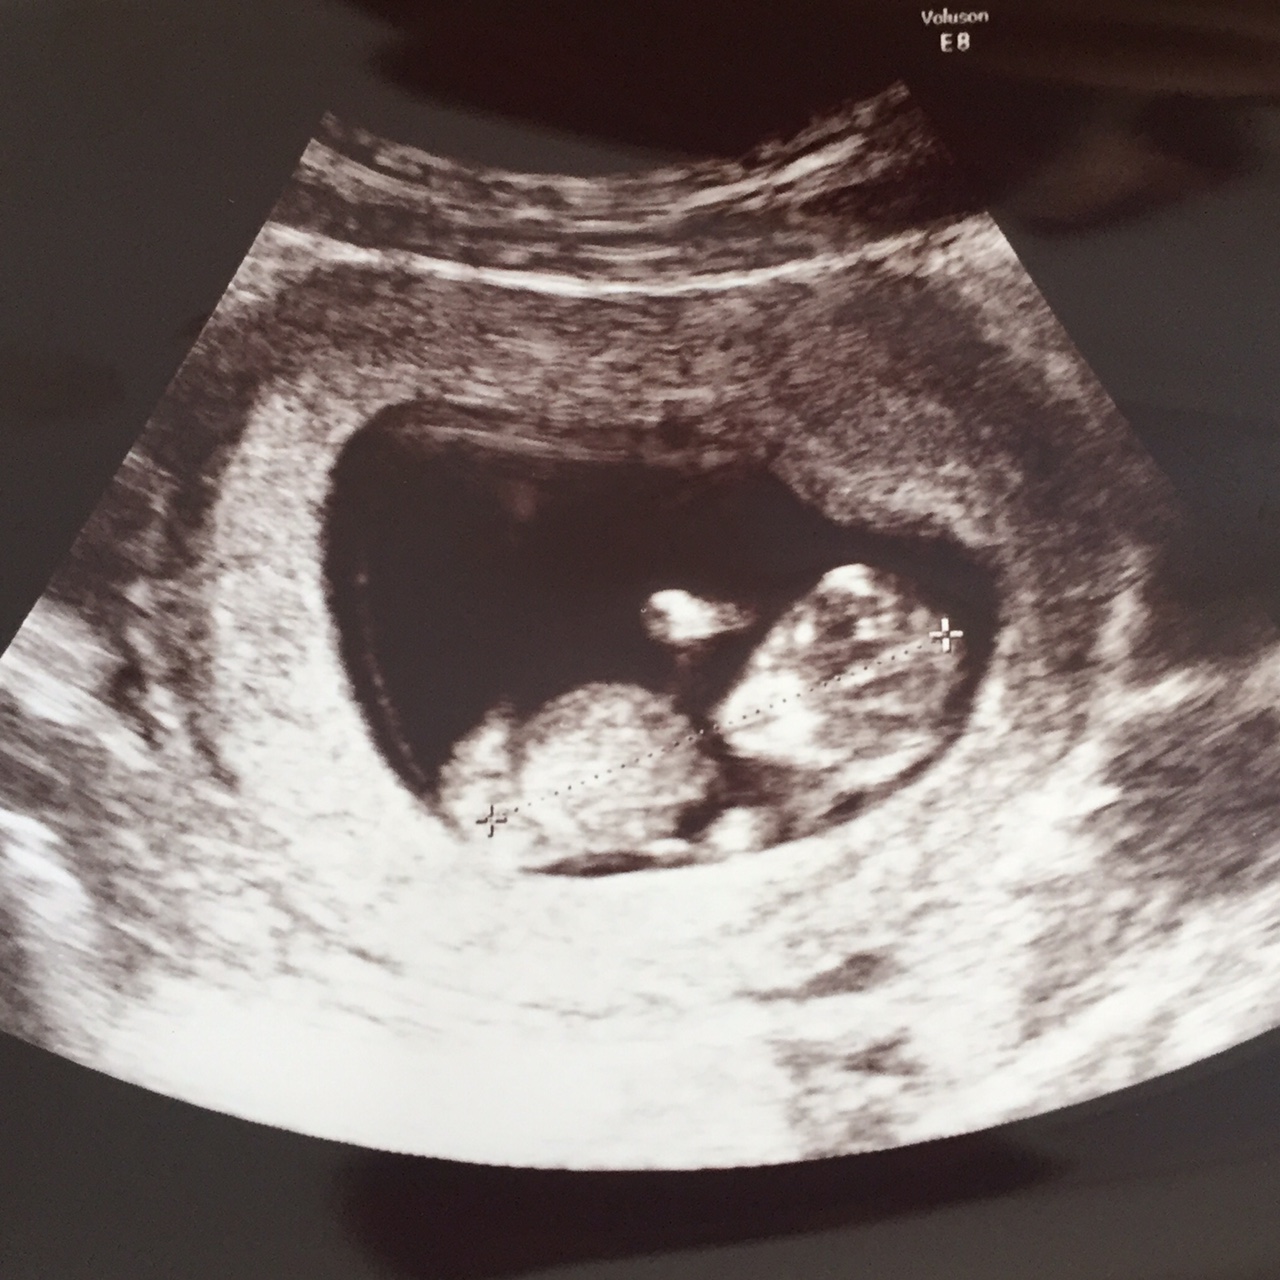

エコー写真を載せます↓

1週間ぶりの我が子は3.3センチに成長ヽ(=´▽`=)ノ